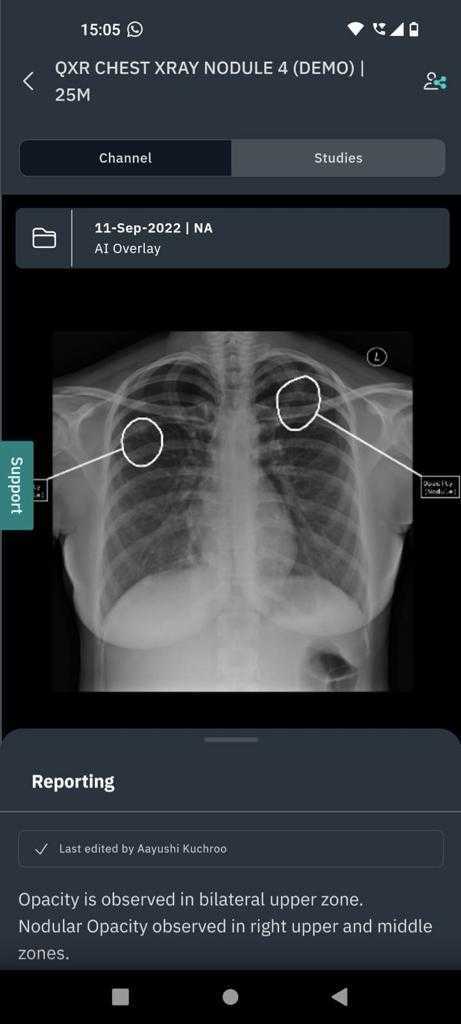

qXR, deep learning AI software swiftly analyses Chest X-rays to triage scans for patients with lung cancer suspicion, enhancing efficiency and shortening time to diagnosis

qXR is AI-powered X-ray software which will be utilised for triaging CXRs immediately after they have been captured. This triage should allow for quicker and more accurate reporting. The project investigates the impact of AI triage of CXRs against routine non-triaged reporting on time to CT and final diagnosis of a patient. The triage alert could lead to faster reporting of suspicious X-rays reducing the wait time for CT appointments. qXR double-read also enhances accuracy of reporting, potentially improving lung cancer detection. The project tests AI CXR triage using qXR across NHS sites, assessing clinical effectiveness, economic viability, and integration. Data collection measures impact on Lung cancer diagnosis time, influencing NOLCP implementation.

In a recent study conducted with a high sensitivity operating point, qXR had a specificity of 83% on normal versus abnormal triage. The false positive rate would be around 17% (Diagnostics 2022, 12(11), 2724).

In a study conducted by Qure.ai with Dubai Health Authority and the University of Sharjah to

evaluate the effectiveness of qXR in detecting lung nodules on CXRs which can be a potential

case of cancer, results showed that qXR had a higher sensitivity of 0.93 as compared to the radiologists’ sensitivity of 0.758. The negative predictive value (NPV) was also high for qXR at 0.956 compared to radiologists (0.87) at 95% confidence interval.